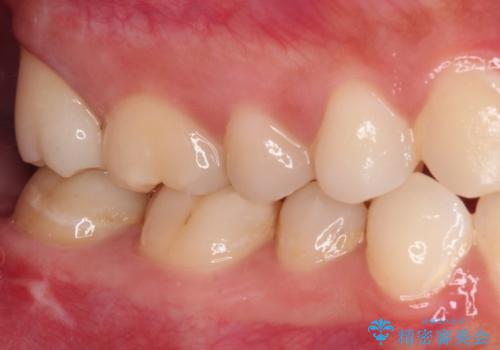

親知らずの抜歯により歯を覆っていた歯肉が切除され、不快感の原因のひとつでもあった歯周ポケットが改善され、奥歯を気にせずに生活できるようになりました。